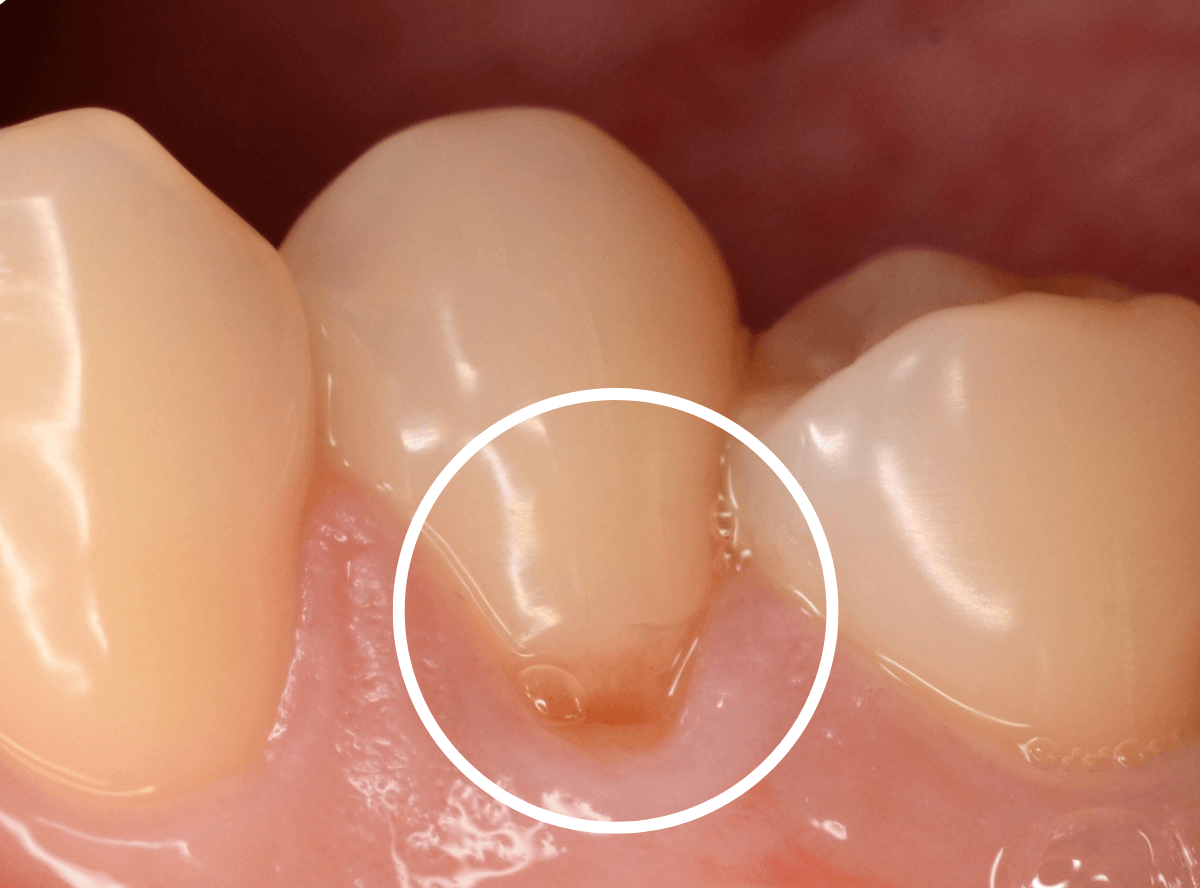

時々、下の奥歯がしみるという症状で、久しぶりに来院された患者さんです。

風を当てる機械でしみる場所を探ってみると、歯の付け根あたりでとても反応がありました。

典型的な知覚過敏といっていいでしょう。

先ほどの画像ではよくわかりづらかったですが、しみる部分を上から見てみると、少し凹んでるのがわかりますでしょうか。

これは、過度な歯ブラシや歯ぎしりなどが原因で歯の側面が摩耗している状態です。

何も感じない方も多く、その場合はあえて何もしない事も多いのですが、今回のように、大きな知覚過敏症状が出てしまう事もあります。

今回のように目に見えて凹んでる部分が見られる場合は、対処が簡単な事が多いです。

こちらの写真でもわかりづらいですが、摩耗した部分に、レジンを少し盛ってあげる。

これだけで、劇的に症状が治まる事がほとんどです。

今回も、症状は劇的に緩和されました。

ただし、過度な歯ブラシや歯ぎしりが続く場合、レジンも短期間で外れてしまう事も多いですので、歯ブラシの仕方を変えたり、歯ぎしり防止のマウスピースを作るなどの対処も一緒に考える必要があります。